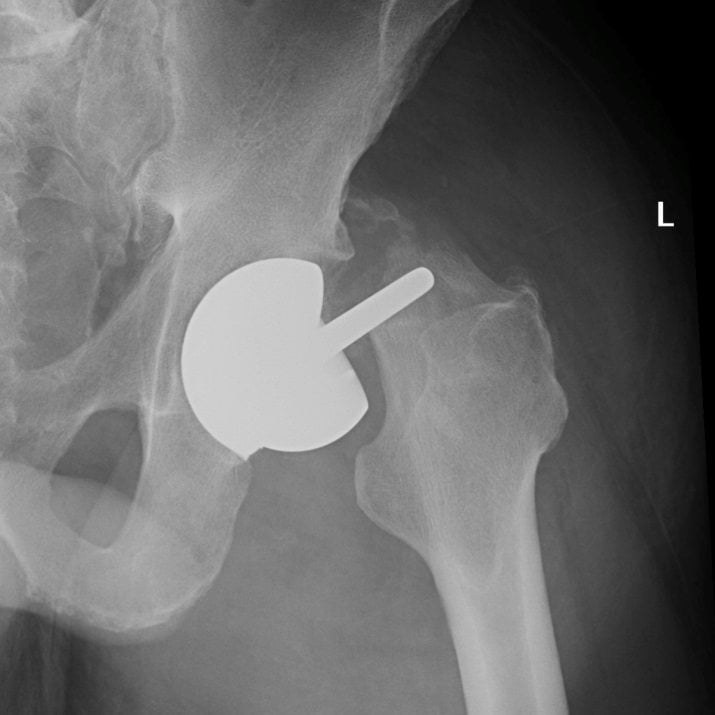

Эндопротезирование тазобедренного сустава: фото и схемы

:max_bytes(150000):strip_icc()/x-ray-illustration-of-hip-replacement-1254389829-281a949198324333972a407cc2e90760.jpg)